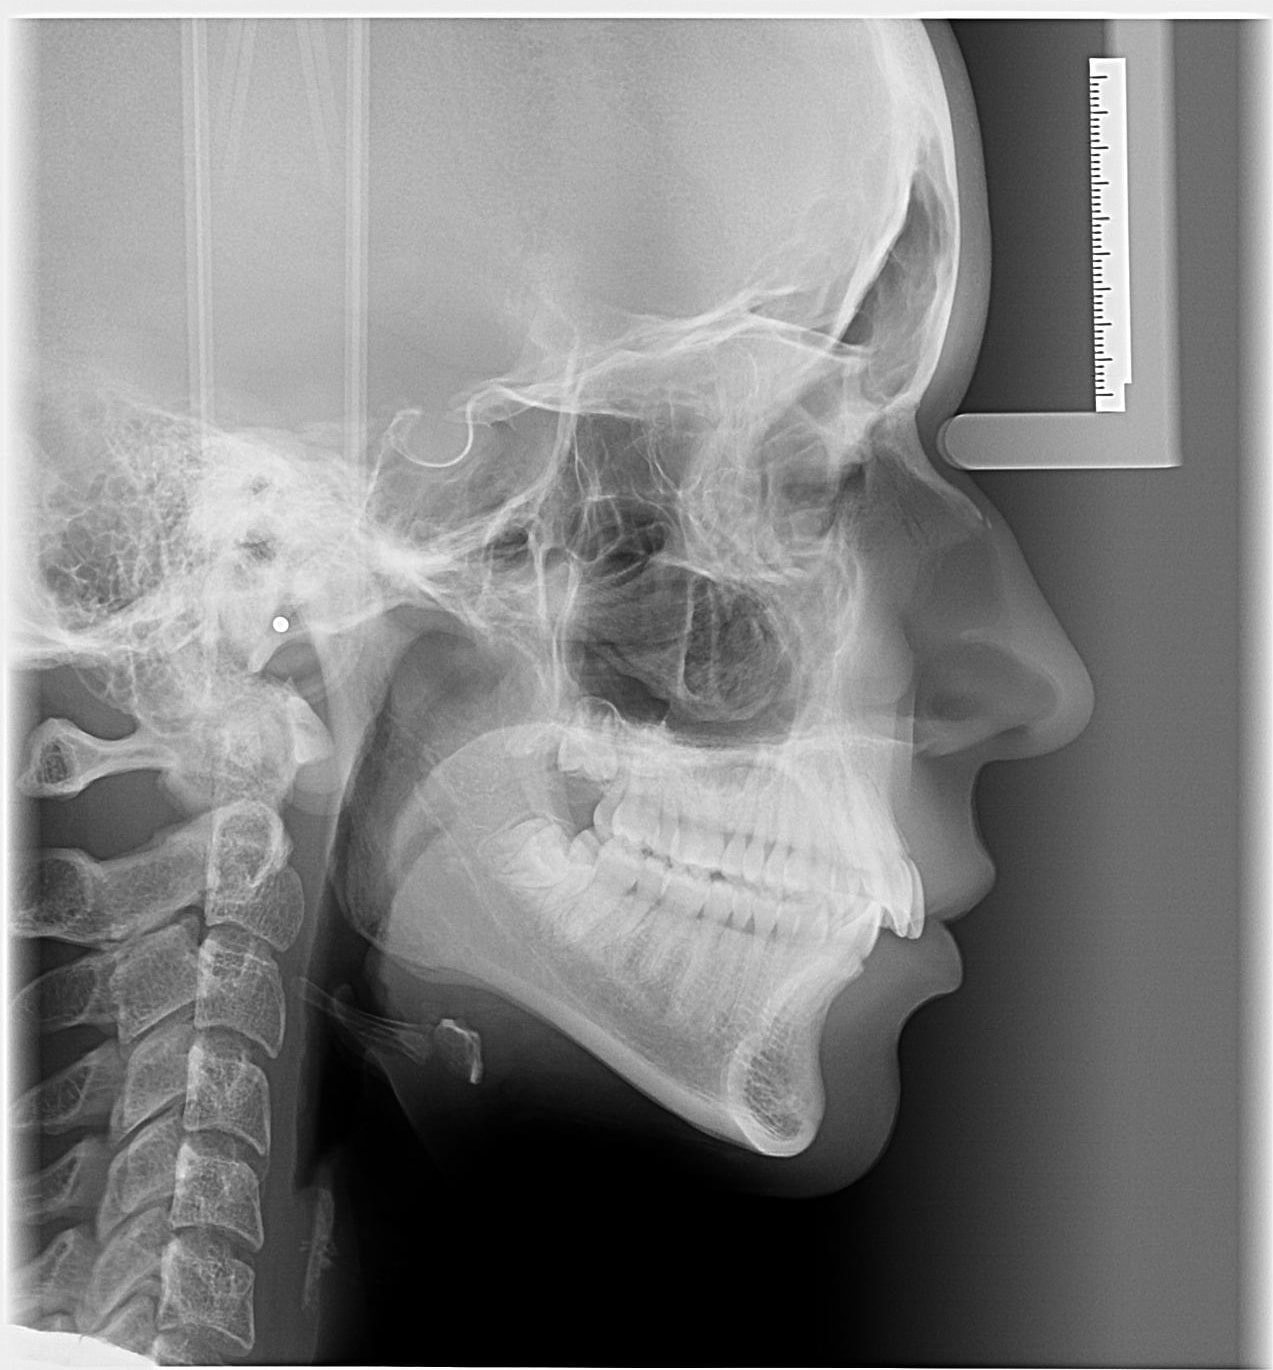

TELERRADIOGRAFIA LATERAL: